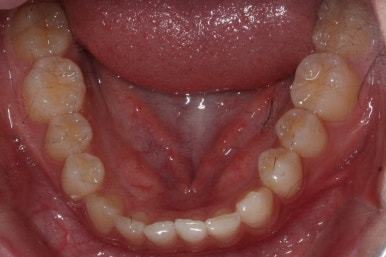

마무리 때의 사진입니다.

윗니만 부분교정하였지만 교합에도 이상 없이 매복되었던 송곳니는 매우 잘 위치를 잡았습니다.

송곳니 부위는 다시 틀어지지 않게 하기 위해 유지철사를 붙여주었습니다.

총 치료기간은 20개월 소요 되었습니다.

부산매복치아교정 상악 부분교정을 통해 매복치를 교정해준 이번 치료의 전후사진 비교입니다.

썩은 유치 대신 영구치 송곳니는 매우 자연스럽게 위치되었습니다. 아랫니는 교정하지 않았기 때문에 약간 삐뚠 느낌은 남아있지만 맞물림은 크게 문제가 없게 마무리 되었습니다.